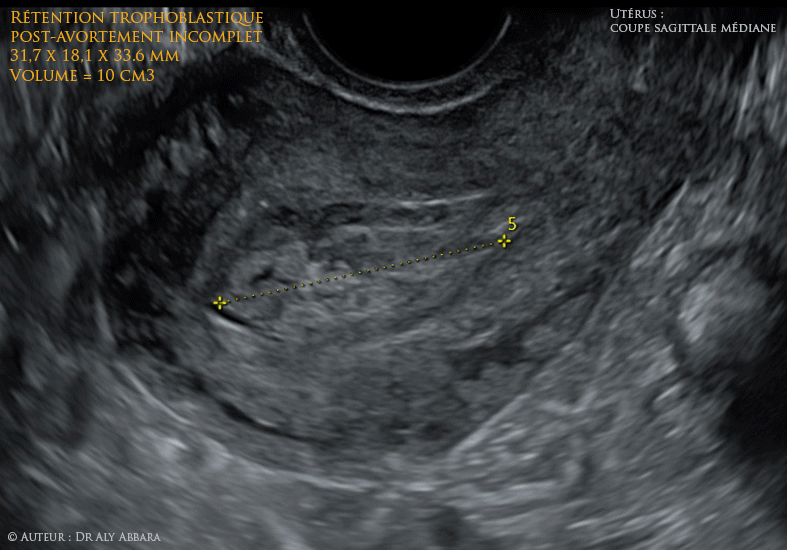

- Anomalie vasculaire utérine de type " shunt artério-veineux ou pseudo anévrysme " mis en évidence deux semaines après une révision utérine (par simple aspiration) pour rétention trophoblastique de 10 cm3 suite à un avortement incomplet (6 semaines auparavant) d'une grossesse de 8 SA.

La troisième image (autodiaporama) montre l'aspect de la rétention trophoblastique chez la même patiente, 4 jours avant l'acte opératoire.